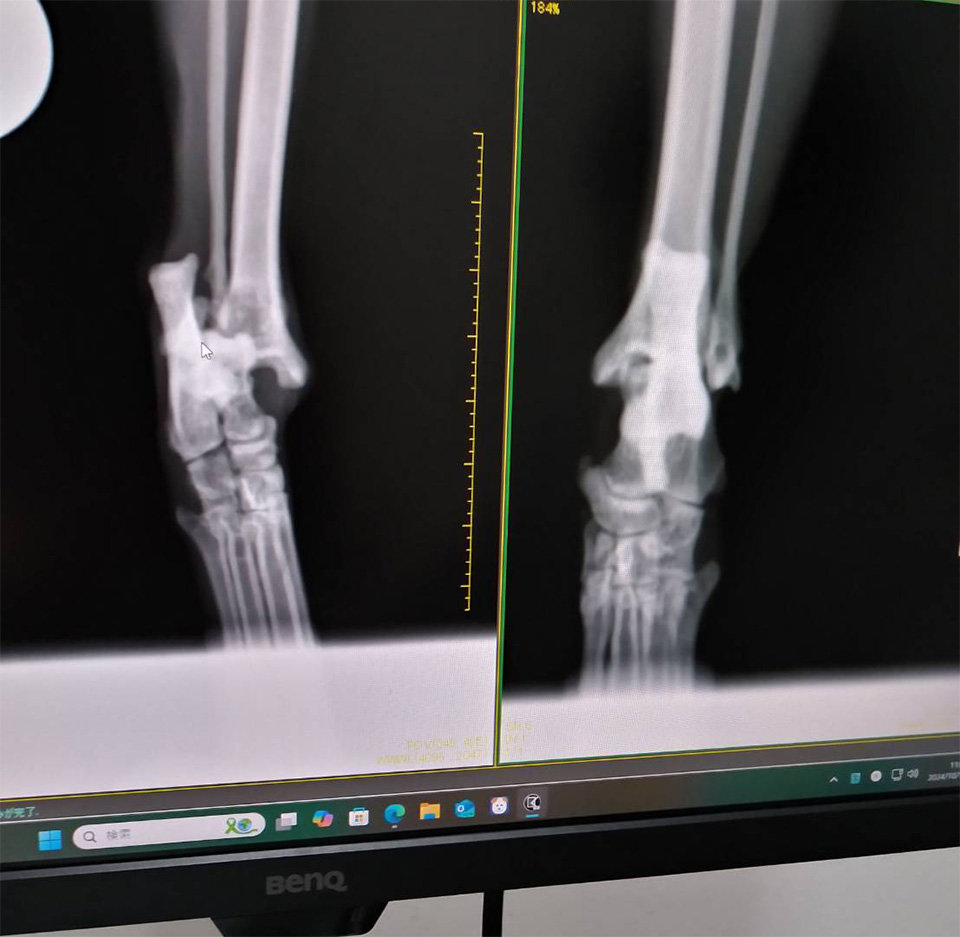

腫れた脚を引きずりながら歩いていたため、保護されたエリ。診察の結果、関節内骨折が判明しました。そのまま生活した場合、骨折や脱臼を繰り返し、さらなる大怪我につながる可能性があるそうで、大怪我を防ぐためには手術が必要です。元気に歩けるようになり、新しい家族が見つかるよう、ウェルカムチャレンジで医療費を支援いたします。